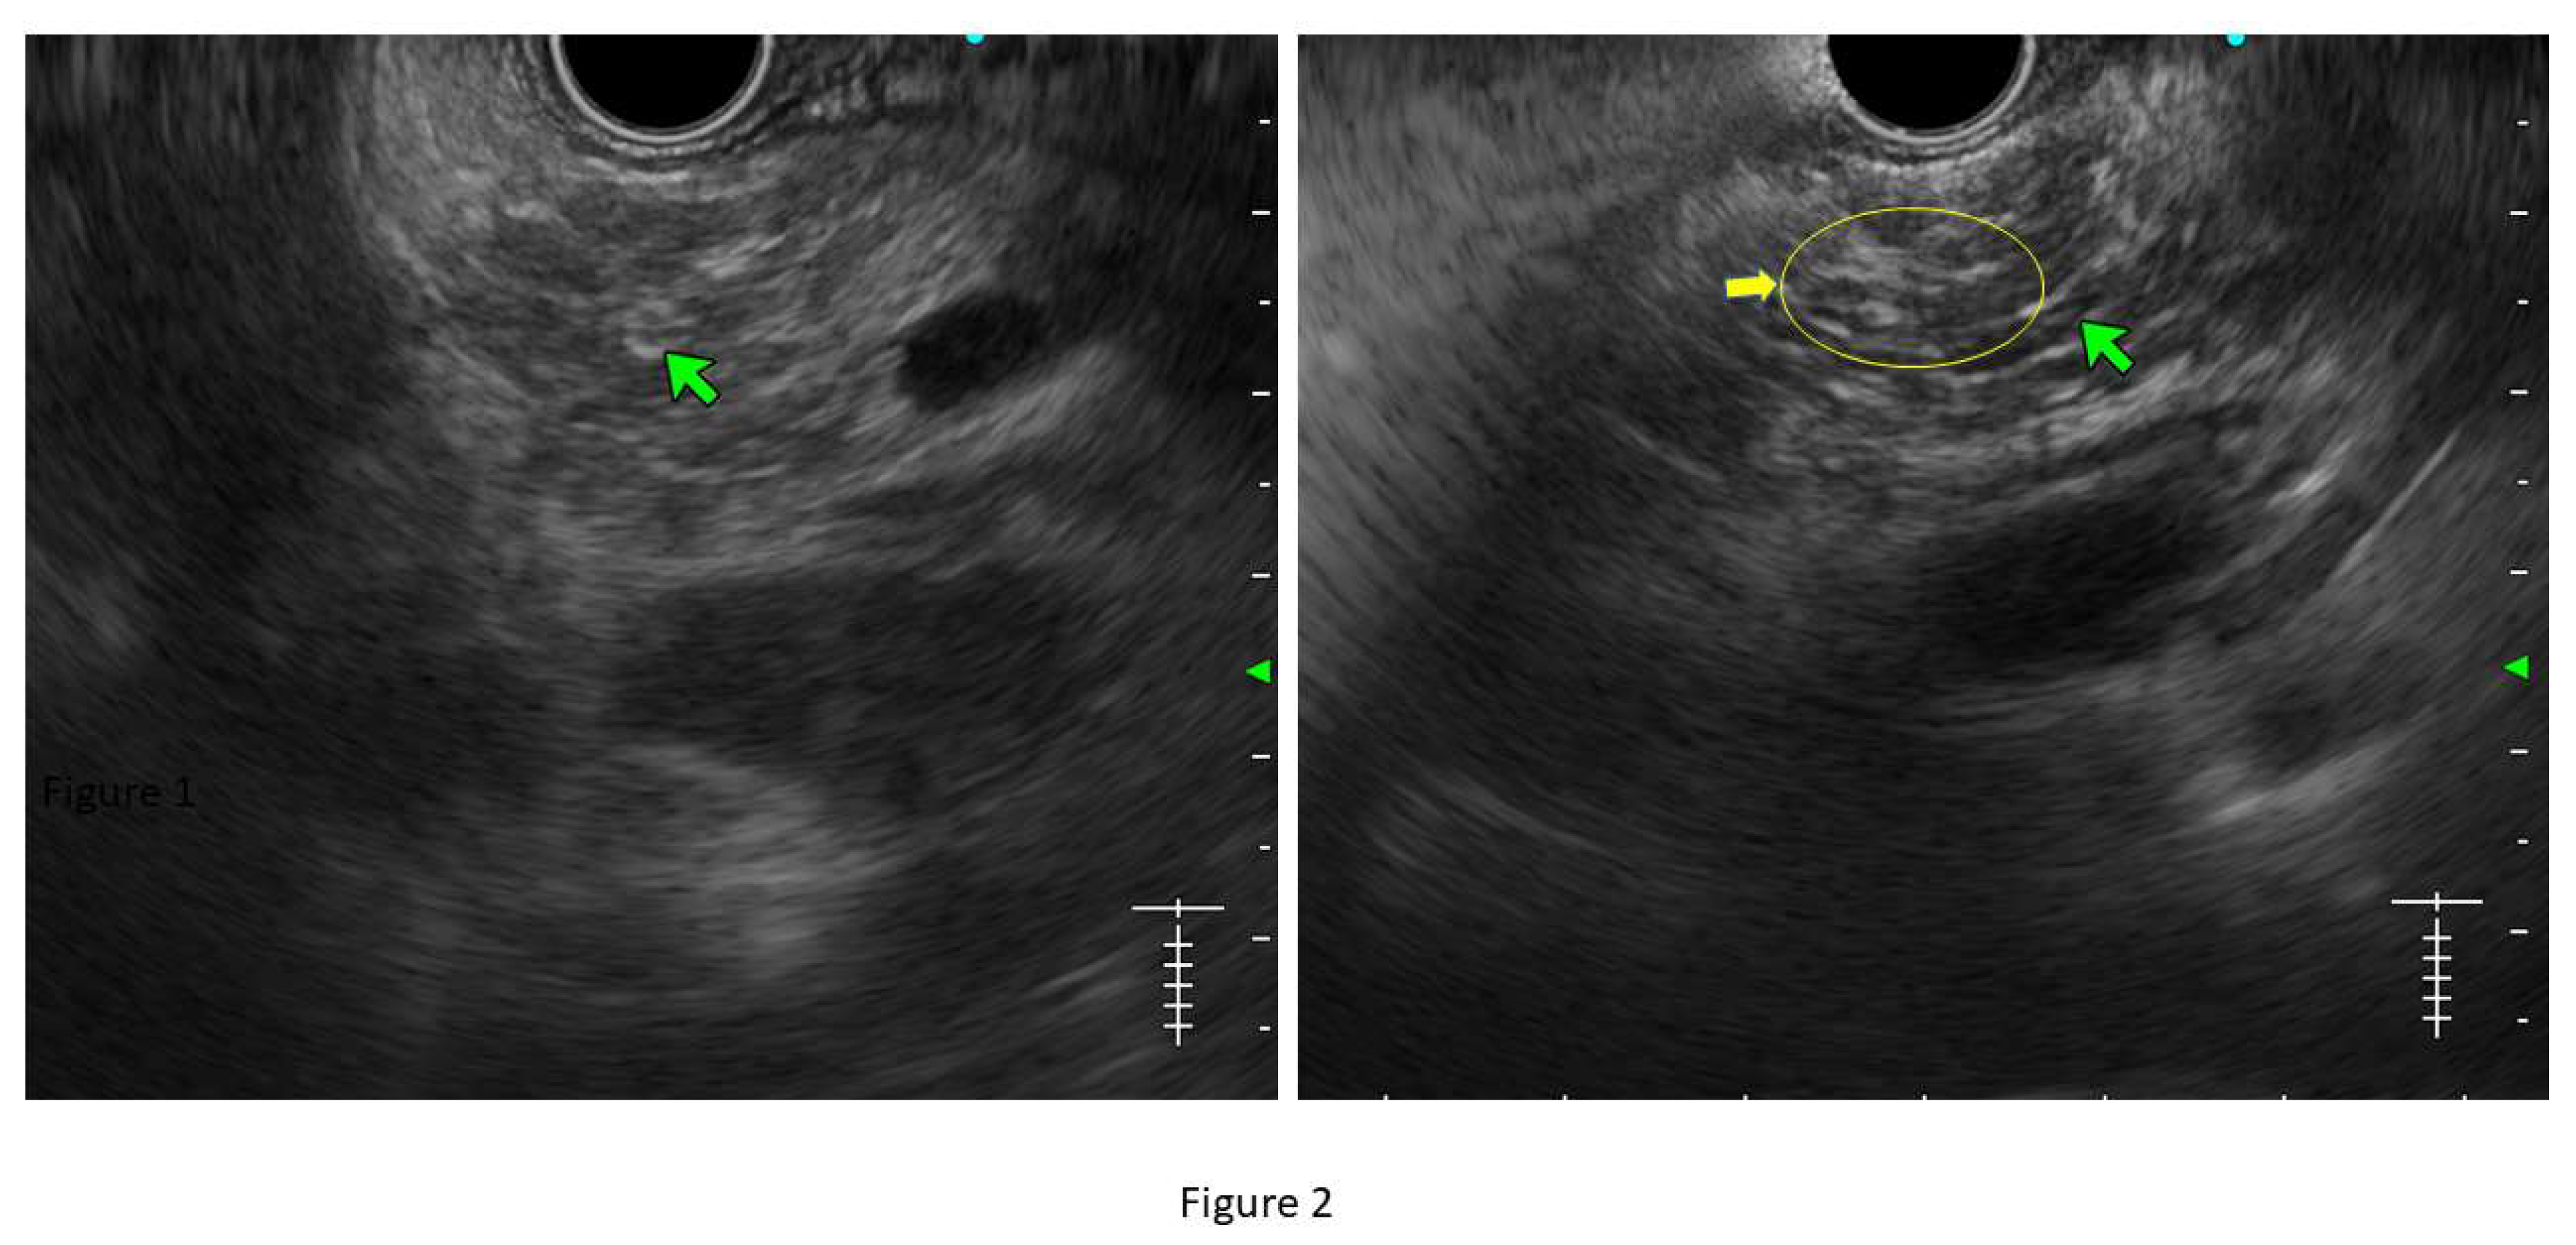

Figure 3. Showing hyperechoic foci without shadowing (yellow arrow).

• Hyperechoic foci without shadowing: Echogenic structures of ≥3mm in length and width without any posterior acoustic shadowing are defined as ‘hyperechoic foci without shadowing’ in the JPS definition. In standard definition, it is included under ‘hyperechoic foci.’ At least 3 such foci need to be present to be described as abnormal. The presence of acoustic shadowing signifies calcification. Histologically, they correspond to focal fibrosis. (Figure 3)